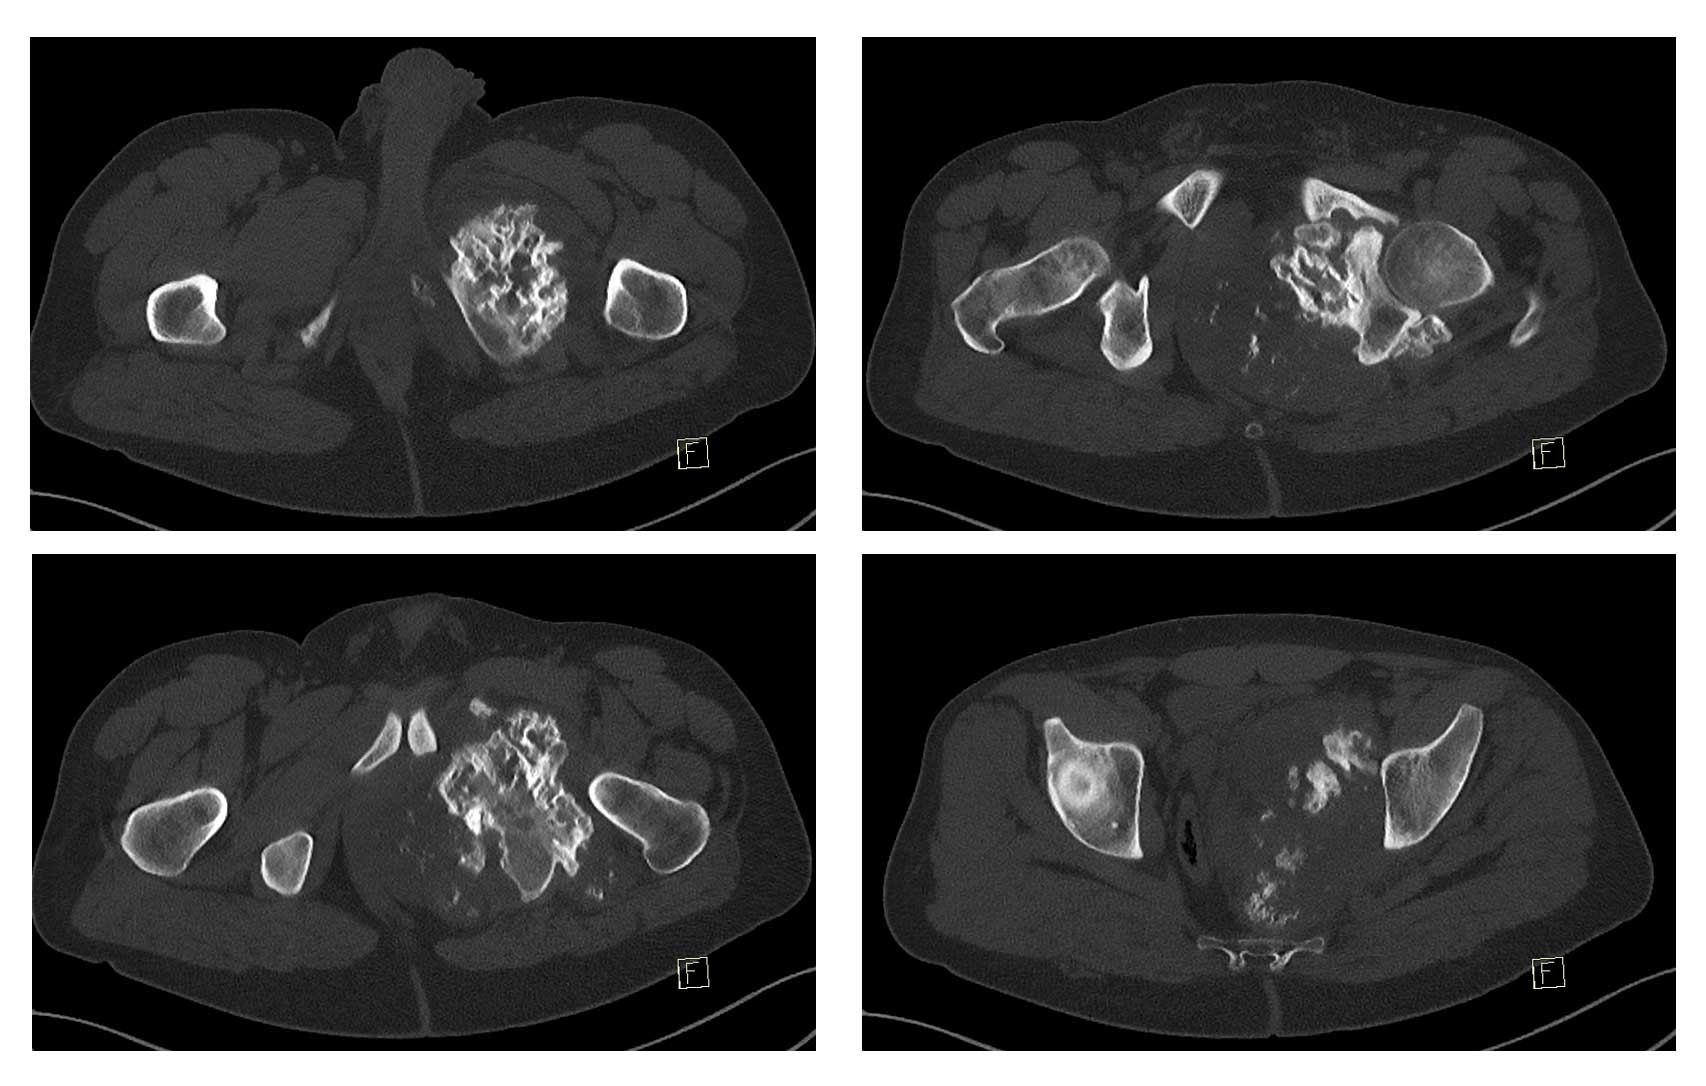

Ameliyat Öncesi: Röntgen ve 3BT’de sol asetabulum ve pubik kol kaynaklı obturator foromani ve hemipelvisi dolduran düzensiz sınırlı sklerotik tümör dokusu görülmekte.